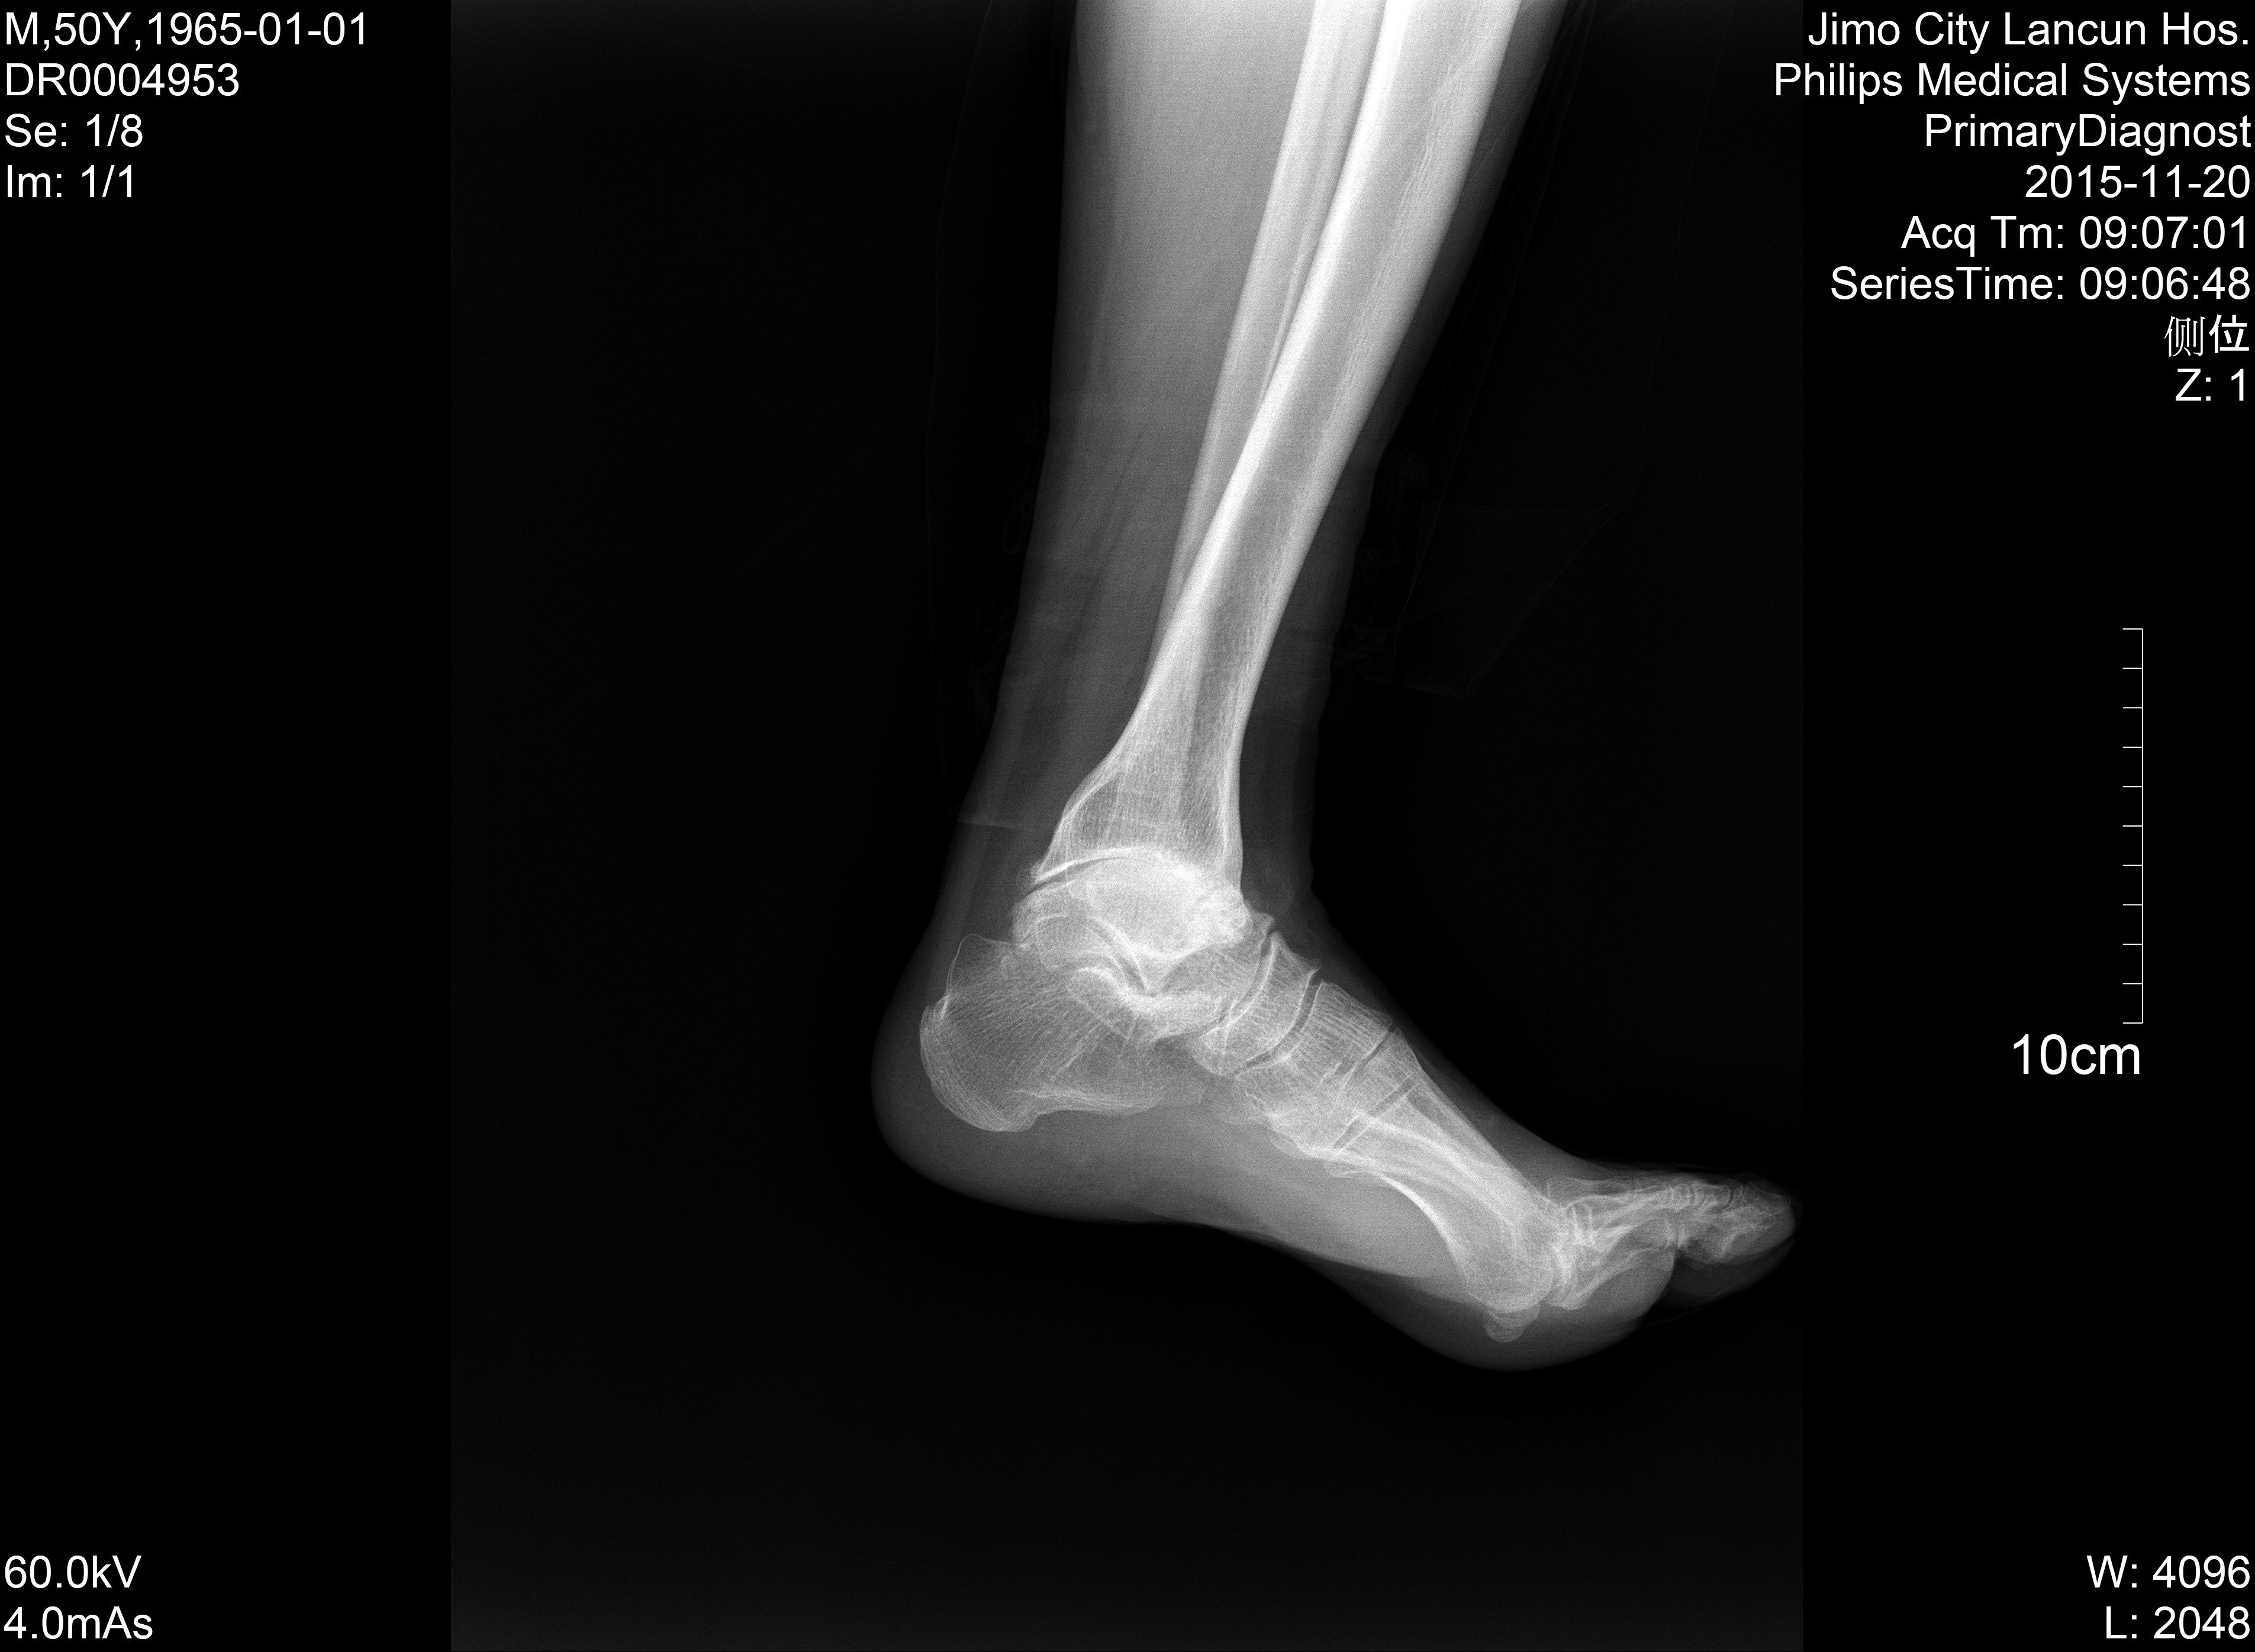

X13860:典型病例

前些天,巡查病例发现,较为典型,上传共享.

胫骨远端膨大,胫距关节面不规整,距骨变扁密度增高,跟骨短小,考虑踝关节大骨关节病。

典型大骨节病